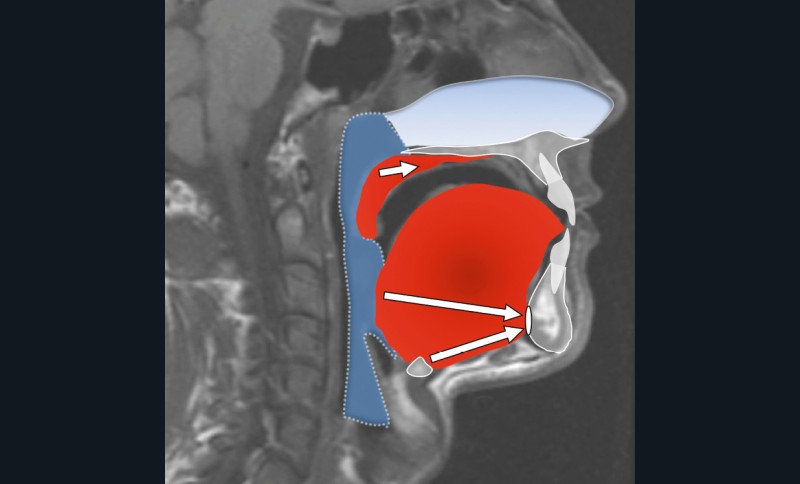

Le collapsus pharyngé à l’origine du SAOS peut résulter de mécanismes variés, souvent associés. L’hypertrophie des tissus mous (amygdales, base de langue, parois pharyngées) en est l’une des causes possibles, fréquemment liée au surpoids observé dans cette pathologie.

L’étroitesse squelettique peut également être impliquée (rétromandibulie, hyperdivergence, endognathie) [1] (fig. 1-4).

Plusieurs approches chirurgicales ont été décrites : les chirurgies des tissus mous visant la désobstruction pharyngée, les chirurgies squelettiques destinées à élargir le calibre pharyngé et, plus récemment, les interventions visant à augmenter le tonus musculaire lingual par stimulation du nerf hypoglosse (fig. 5).